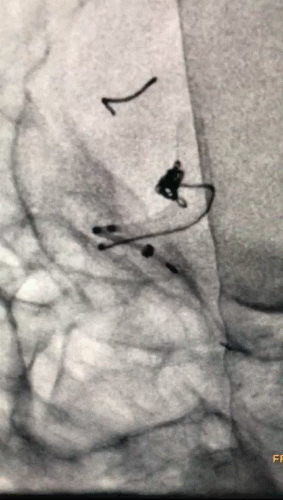

3.3)

填入5个超软圈,美敦力Prime系列对瘤壁压力非常低,对脆弱的血泡样动脉瘤安全有保障;弹簧圈圈体非常柔软,有利于致密栓塞,阻隔血流。

APB 3-8-3D、APB 2-4-3D 、APB 2-4-2D,APB 2-3-2D,APB 1-1-2D